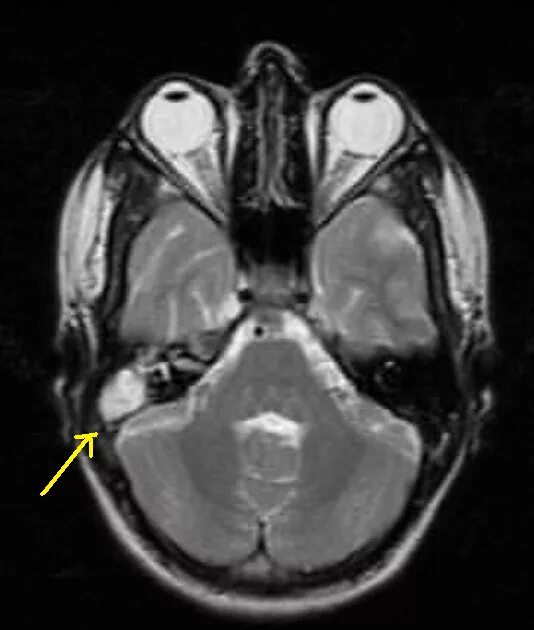

Мрт височных костей в режиме dwi